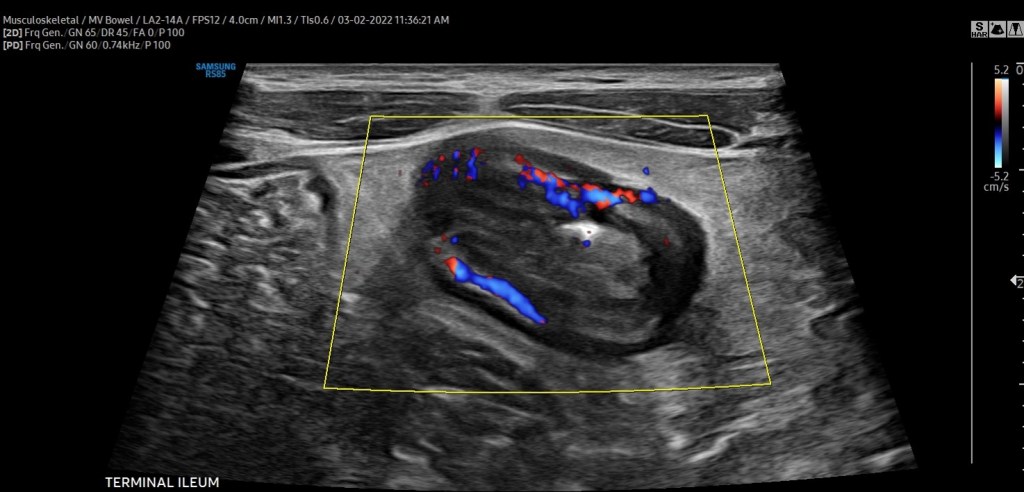

Intestinal Ultrasound (IUS) is an abdominal ultrasound performed during a routine clinic visit without preparation, fasting, or contrast to assess both the colon and the small intestine (terminal ileum most frequently) for the presence of disease activity. Probes are placed over the abdomen and the provider looks at images of the small and large bowel.

The beauty is that, unlike procedures and other image modalities available to assess disease activity of inflammatory bowel disease, IUS can be performed without any preparation or fasting,” said Dr. Chavannes. “In the setting of active disease, patients can have a thickened appearance of the wall of the bowel (termed increased bowel wall thickness) in both the small intestine and the colon, which can be detected via ultrasound.”

In addition, by using color Doppler, a feature that assesses the velocity of blood flow within and around the bowel wall, gastroenterologists can demonstrate inflammatory activity in the bowel wall. IUS can also detect IBD complications, such as fistulas, abscesses, or strictures (narrowing) of the bowel.

“Our expectation is that, with effective therapies, the aforementioned features of disease activity should improve or even disappear over subsequent clinic visits. If they do not, we now have an objective tool available in the clinic that can assist clinical decisions, such as ordering further investigations or even optimizing or changing therapy. Improvement of bowel wall thickening or decrease in color Doppler signaling is a reassuring sign that treatment is working. Lack of improvement signifies that optimization or changes in therapy should be considered,” explained Dr. Chavannes.

“Intestinal ultrasound is precise, we monitor bowel wall thickness down to the 0.1 mm. We are now able to make informed decisions with patients together, assessing their disease objectively in real-time so we can be aligned with our treatment goals. This reduces misunderstanding and may lead to better treatment adherence and improved outcomes,” said Dr. Dolinger.